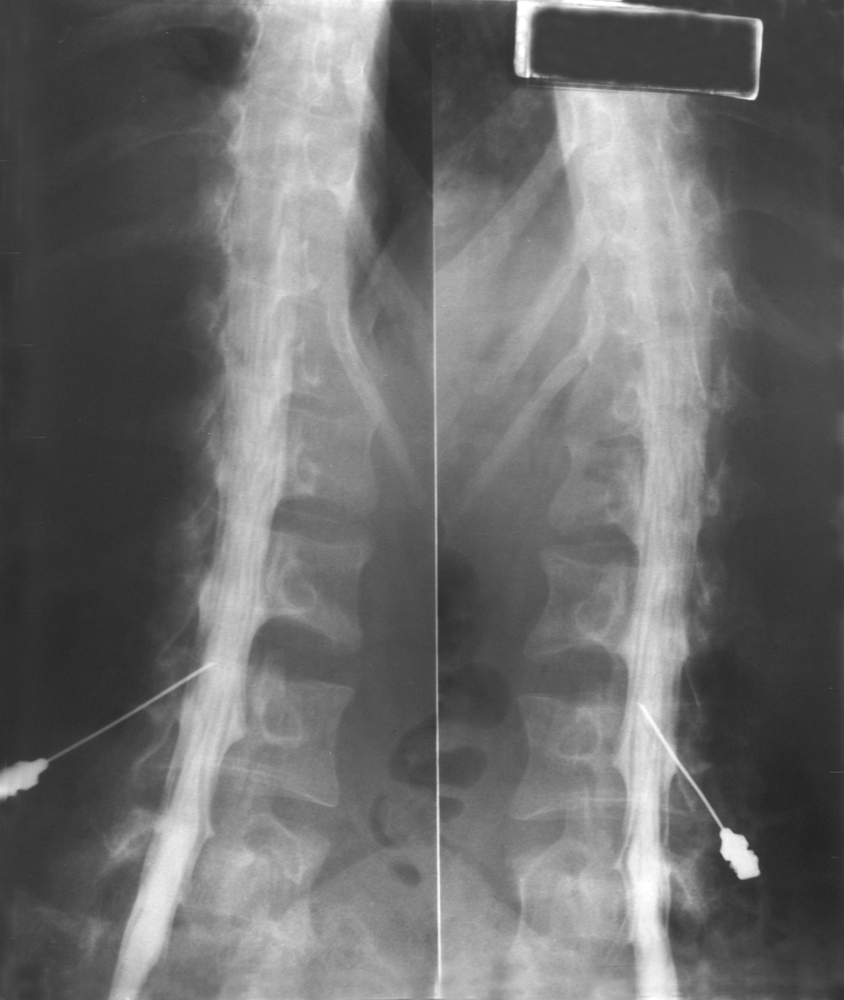

В зависимости от направления распространения контраста различают 2 вида миелографии: восходящую и нисходящую. В первом случае спинномозговую пункцию проводят в поясничном отделе позвоночника, во втором – в шейном его отделе.

Кожу в области предполагаемого прокола троекратно обрабатывают растворами антисептиков, после чего послойно обкалывают этот участок раствором анестетика. Пункционную иглу под контролем флюороскопа вводят взрослому на уровне между остистыми отростками 3 и 4 поясничных позвонков по срединной линии спины под небольшим углом кверху (параллельно остистым отросткам). Когда игла пройдет все структуры, проколет паутинную оболочку и окажется в субарахноидальном пространстве, врач, осуществляющий пункцию, ощутит как бы провал. После этого из иглы достают мандрен и наблюдают выделение по каплям спинномозговой жидкости. Несколько мл этой жидкости сразу же направляют в лабораторию на анализ, после чего подсоединяют к игле шприц и вводят контрастное вещество. Затем иглу вынимают, кожу повторно дезинфицируют, и пациент меняет положение на столе – ложится на живот лицом вниз.

И снова под контролем флюороскопа рентгенолог медленно наклоняет стол – при осуществлении поясничного прокола он наклоняет головной конец, а при пункции шейного отдела позвоночника – опускает ноги. Угол наклона небольшой – он составляет не более 10°С.

В процессе выполнения наклона на мониторе рентгенолог наблюдает распространение контрастного вещества по спинномозговому каналу – обтекание им спинного мозга и других структур. Врач обращает внимание на малейшие отклонения от нормы и при необходимости делает снимки того или иного участка. Для получения качественных снимков пациент должен лежать на боку и не двигаться в момент снимка. Даже небольшое вздрагивание повысит вероятность размытия изображения.